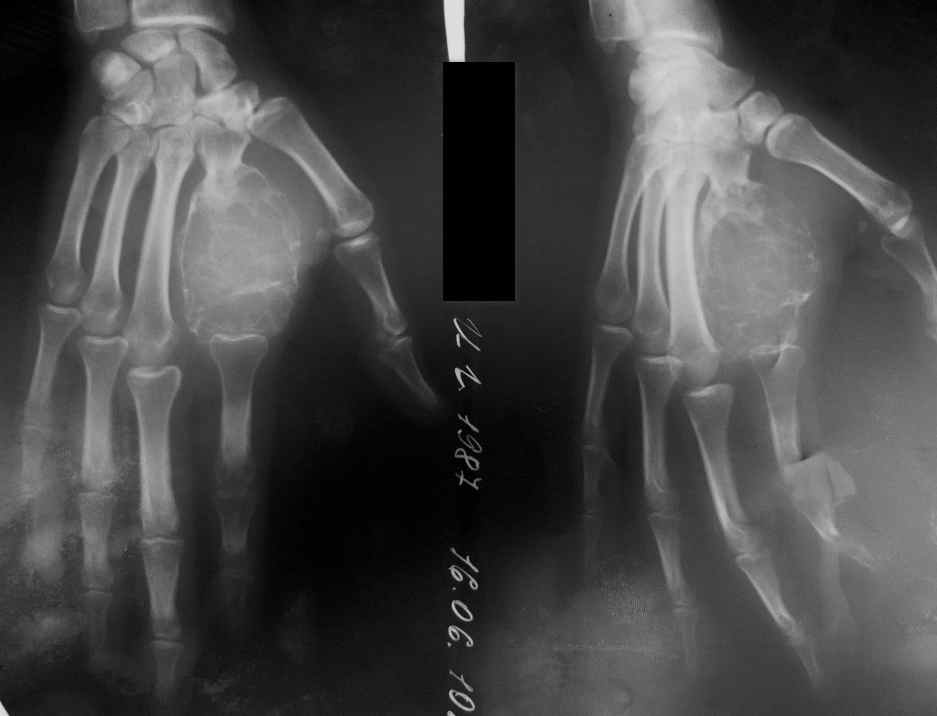

[Ortho] ГКО 2-й пятной кости

Доброго времени суток уважаемые коллеги. К нам обратилась пациентка 23 лет. Вполнена

открытая биопсия. По результатам биопсии выставлен диагноз: Гигантоклеточная опухоль 2-й

пястной кости левой. В настояее время поступила для радикального лечения. Планируем

выполненить резекцию опухоли. Вопрос в материала для замещения деффекта. Есть мысль

выполнить ауцтопластику трансплантатом из малоберцовой кости. Каковы будут мнения по

этому поводу? Заранее большое спасибо за советы.